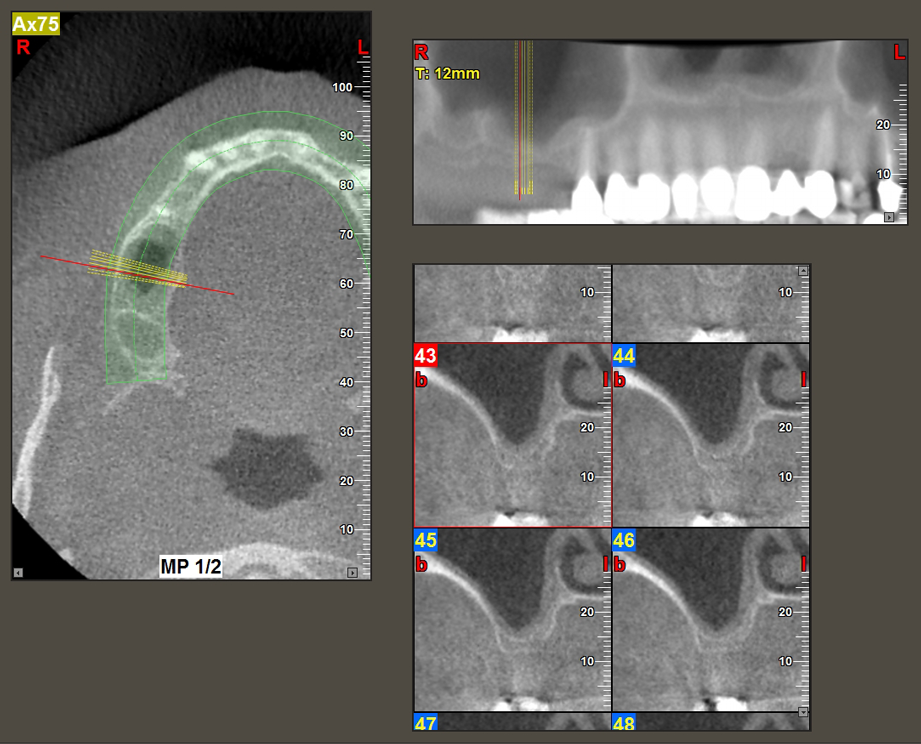

A 49-year-old female patient, a non-smoker and with nothing remarkable in her general medical history, was referred to our oral surgery practice for surgical extraction of tooth 16 and subsequent implantation. After the extraction, the patient experienced mild sinusitis trouble with the resultthat we initially waited six months before carrying out the measure. The residual bone height at the planned implant position measured 3-4 mm (Fig. 1 and 2).

The I2A instrument (diameter 2.0 mm) was then used to perforate the sinus floor intermittently and on the smallest scale possible. This special piezosurgical method ensures that the Schneiderian membrane is not damaged. When the Z25P was used, the membrane was already lifted slightly by the coolant supplied via the instrument tip (Fig. 3). The coolant quantity was just 50% in order to avoid high pressure in the implant bed.

Following an intermediate check (Fig. 4) a further preparation step was performed (Fig. 5). Afterwards, the hydraulic Z35P instrument was used to lift the membrane to the desired position (Fig. 6 and 7). This was followed by further piezosurgical preparation of the implant bed, concluded with a rotary bur and shoulder milling cutter up to the implant diameter of 4.8 mm. Before the implant was inserted, the augmentation material (particle size approx. 0.8-1.6 mm) was introduced underneath the Schneiderian membrane (Fig. 8).